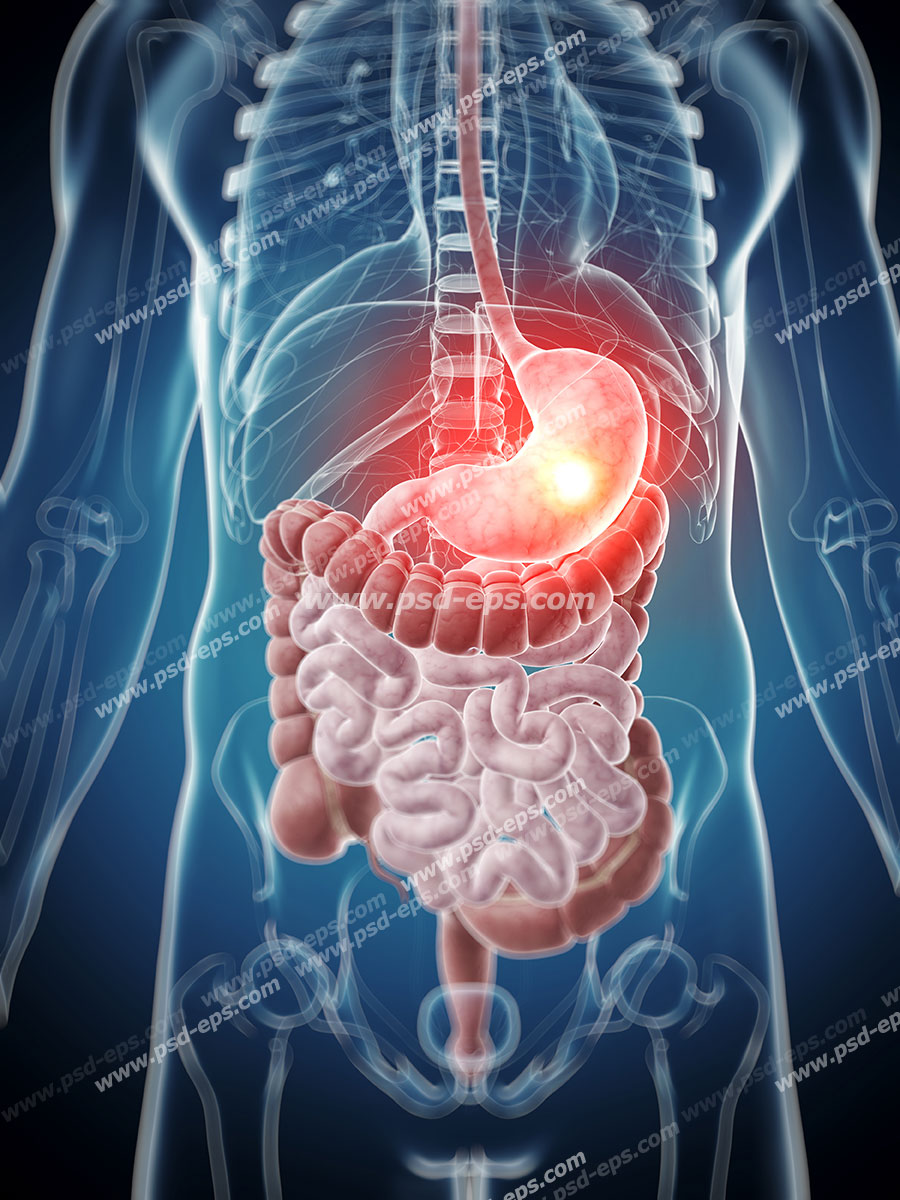

عکس اسکلت بدن انسان با کیفیت. عکس اسکلت عکس اسکلت برای پروفایل عکس اسکلت انسان عکس اسکلت خفن عکس اسکلت بدن انسان با کیفیت عکس اسکلت بدن انسان عکس اسکلت ترسناک عکس اسکلت فانتزی عکس اسکلت فانتزی دخترانه پرچم عکس اسکلت. عکس با کیفیت اسکلت داخلی انسان و درد و گرفتگی در ناحیه استخوان زانو ویژه استفاده در امور تبلیغاتی و تجاری طراحی کاتالوگ بروشور و تراکت با موضوع پزشکی فیزیوتراپی ارتوپد دکتر روماتیسم فیریوتراپ طب فیزیکی. عکس اسکلت بدن انسان زن و مرد آناتومی ساتین 16 سپتامبر 2017. اسکلت داربست بدن است تمام قسمت های بدن روی اسکلت قرارگرفته اند بدن انسان از ۲۰۶ قطعه استخوان تشکیل شده است این استخوان ها طوری با نظم کنار هم قرار گرفته اند که انسان را قادر می سازد حرکات دقیقی داشته باشد.

اسکلت جمجمه و گردن انسان ستون فقرات آناتومی اسکلت جمجمه و گردن انسان ستون فقرات آناتومی تصویر با کیفیت را از لینک زیر می توانید دانلود کنید. ۱ مطلب با کلمه ی کلیدی عکس اسکلت بدن انسان با کیفیت ثبت شده است گالری نسیم جدید ترین و با کیفیت ترین عکس های مناسبتی. عکس با کیفیت آناتومی اسکلت بدن انسان و درد و دیسک در قسمت مهره های ستون فقرات کمر ویژه استفاده در امور تبلیغاتی و تجاری طراحی کاتالوگ بروشور و تراکت با موضوع بیمارستان ها و کلینیک ها و درمانگاه ها و مطب ها پزشکان و.